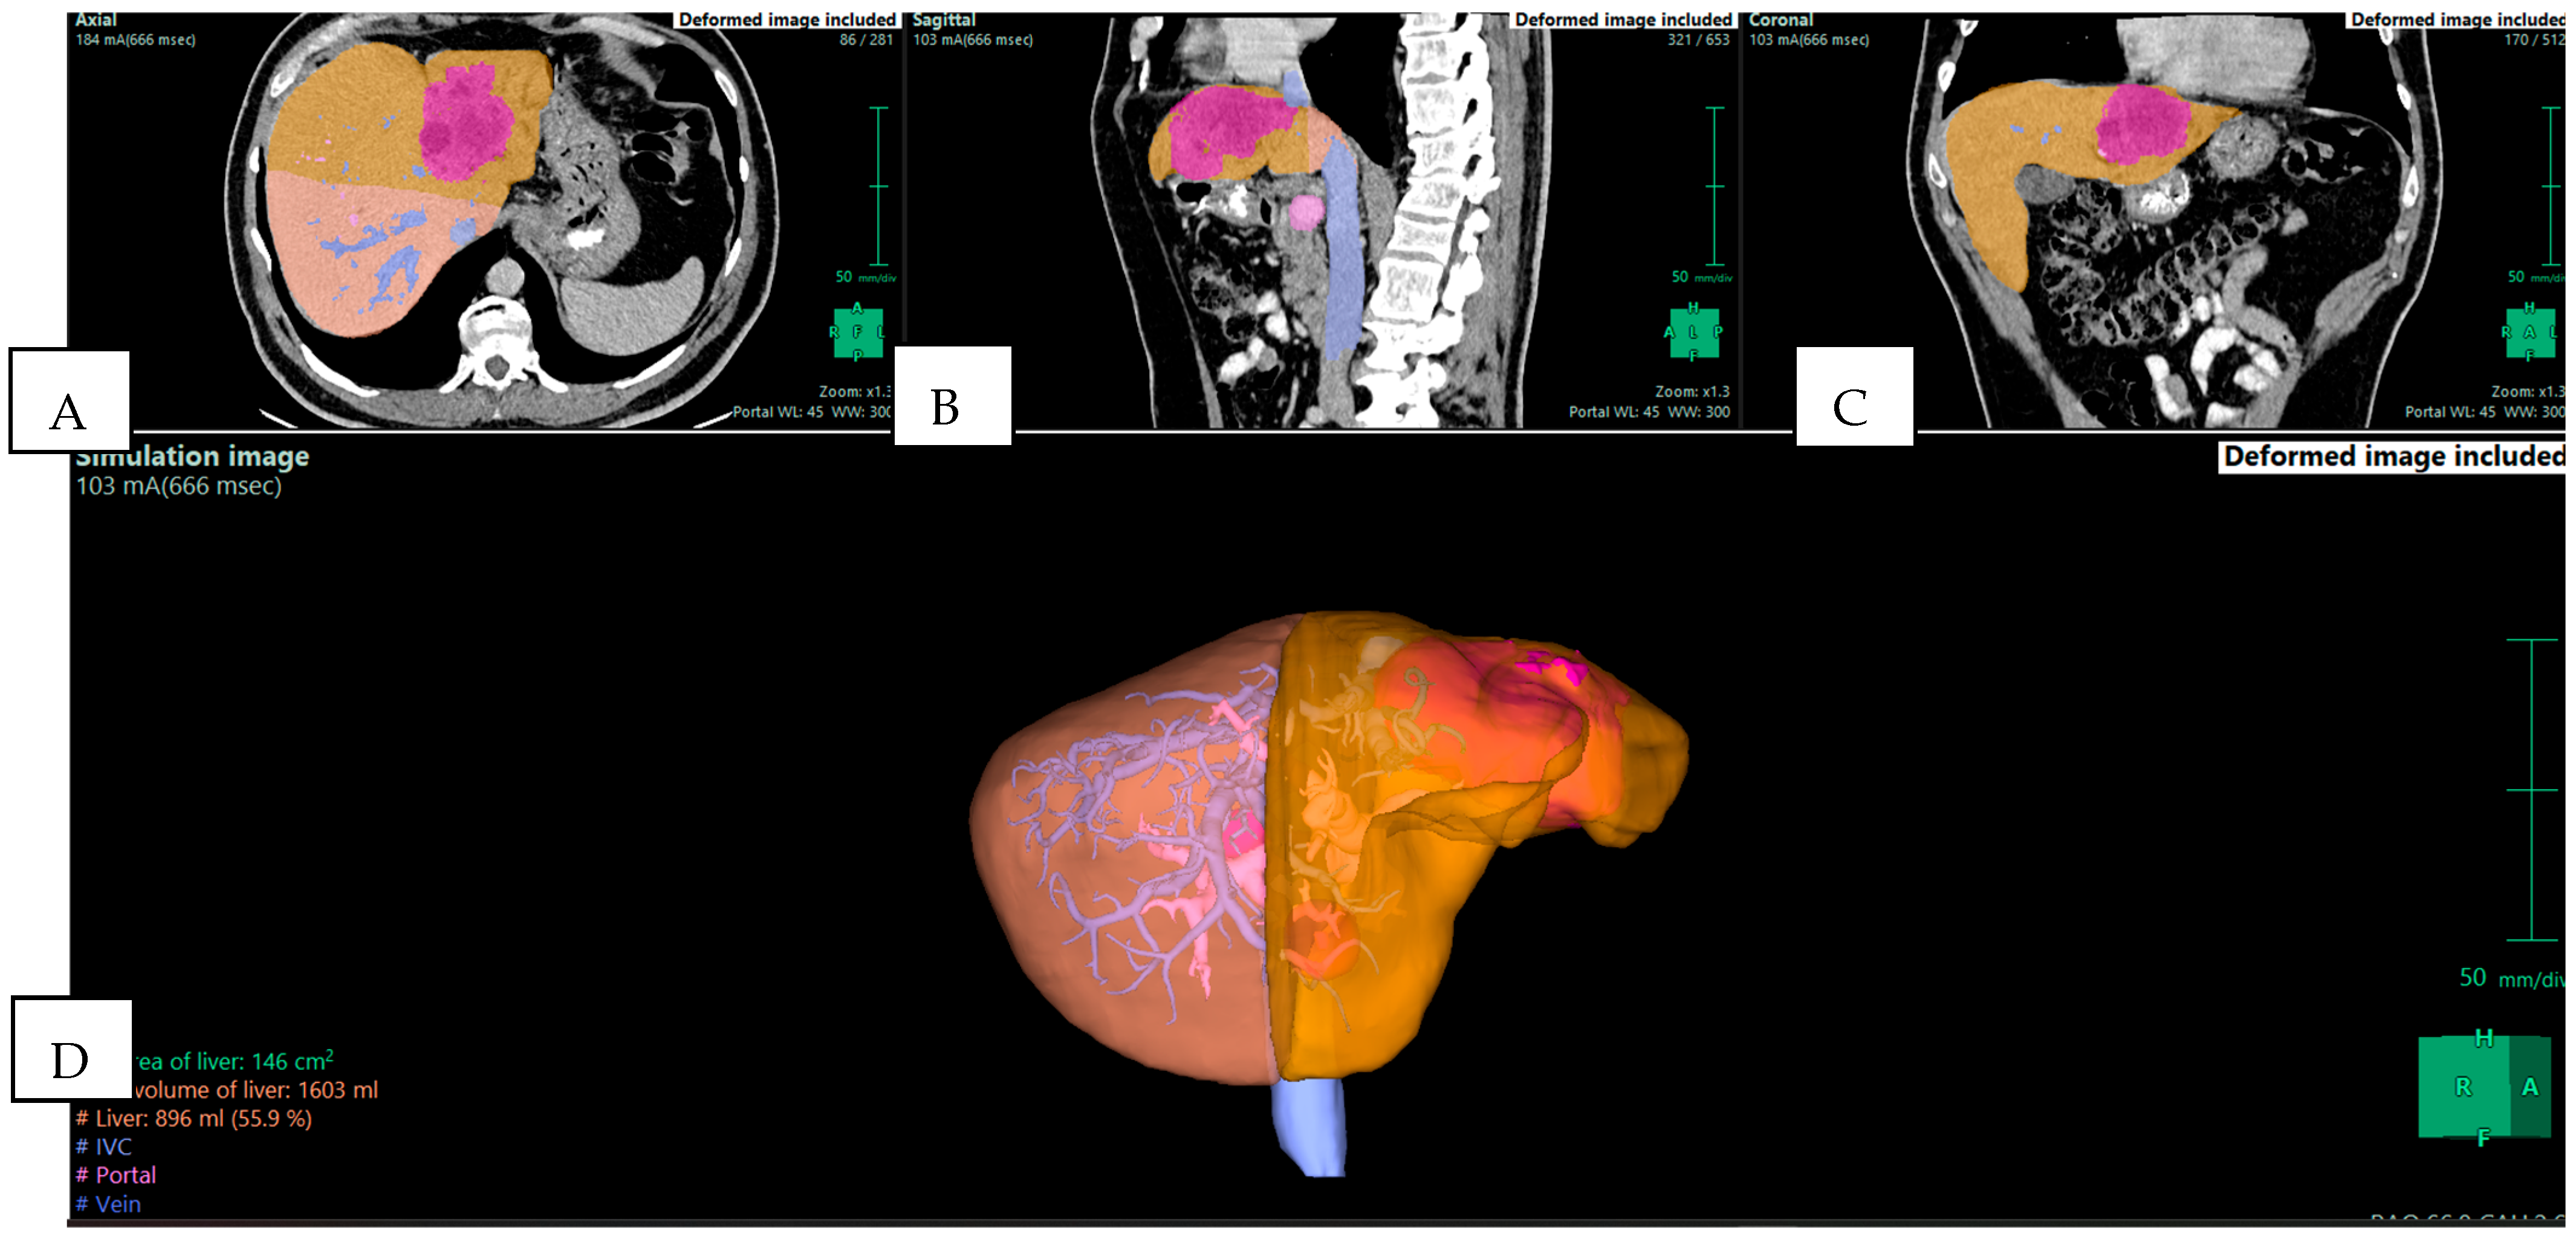

4.2. Intraoperative Applications in Liver Surgery

Liver surgery is one of the main areas where 3D reconstruction has demonstrated its potential. During major resections, a precise understanding of the vascular inflow, venous drainage, and bile duct anatomy is essential, as well as an accurate calculation of the future liver remnant (FLR), which is crucial (Figure 3). Conventional CT can provide this information but often requires the surgeon to mentally reconstruct 3D relationships from 2D slices. Cotsoglou et al. carried out a multicentric international survey and demonstrated that 3D reconstructions significantly improved the recognition of tumor–vessel relations compared with standard CT [4]. Surgeons reported that this information reduced intraoperative uncertainty and allowed for more confident intraoperative decisions.

Figure 3. Preoperative planning of a mass-forming intrahepatic cholangiocarcinoma (iCCA) in the left lobe of the liver in a 57-year-old man. The tumor (pink) is in the left lobe (yellow). The future liver remnant (orange) is calculated for the right lobe and is 55.9% of the total liver volume (TLV), indicating that a left hepatectomy is feasible. (A) Axial plane; (B) sagittal plane; (C) coronal plane; and (D) 3D reconstruction—simulation image. Images derived from anonymized clinical datasets from our institution.